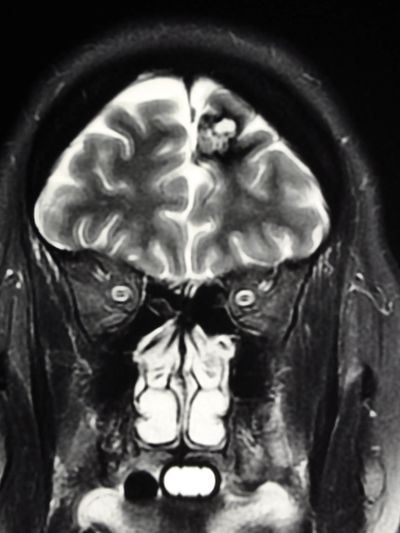

Arteriovenous malformation (AVM) is an abnormal tangle of blood vessels in the brain or spinal cord. AVMs can cause a variety of symptoms, and their severity depends on the size and location of the malformation. Some AVMs may remain asymptomatic and go undetected, while others can cause significant neurological problems. Common symptoms of arteriovenous malformation include:

A: An Arteriovenous Malformation (AVM) is an abnormal tangle of blood vessels, which can occur in the brain or spinal cord. AVMs disrupt the normal blood flow pattern, as arteries (carrying oxygen-rich blood) are directly connected to veins (carrying oxygen-depleted blood) without the usual capillary network in between.